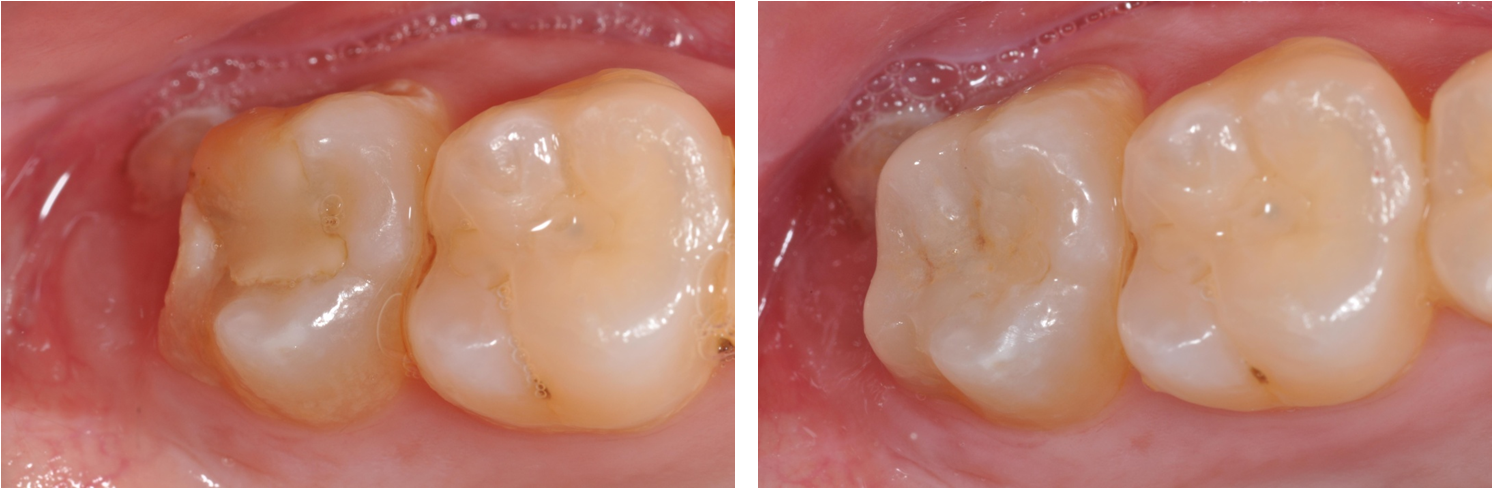

治療前,已補上複合樹脂,二次蛀牙,牙齒敏感

治療後,美觀與功能恢復理想

術前、術後比較